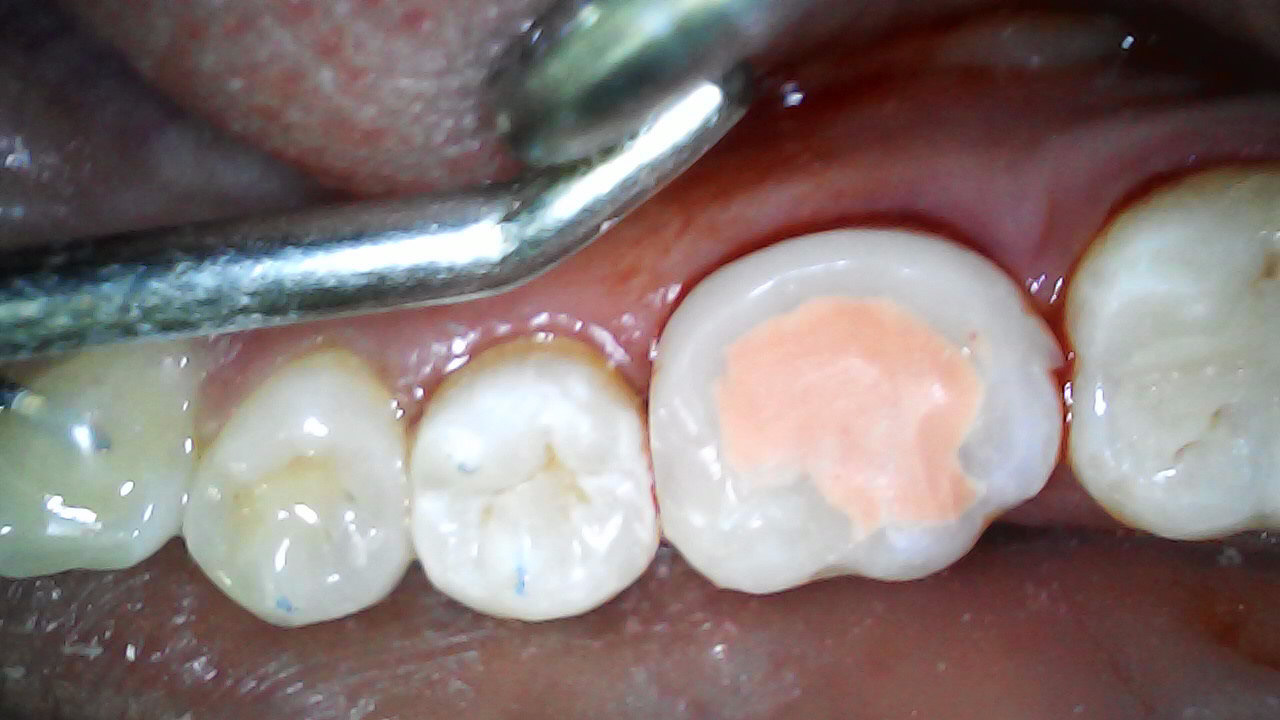

36 restores temporarily with Filtek Supreme A2B. Fuji VII to monitor pulp response 3 months

3 months later - Pulp remained vital, tooth asymptomatic (mesial overhang removed)